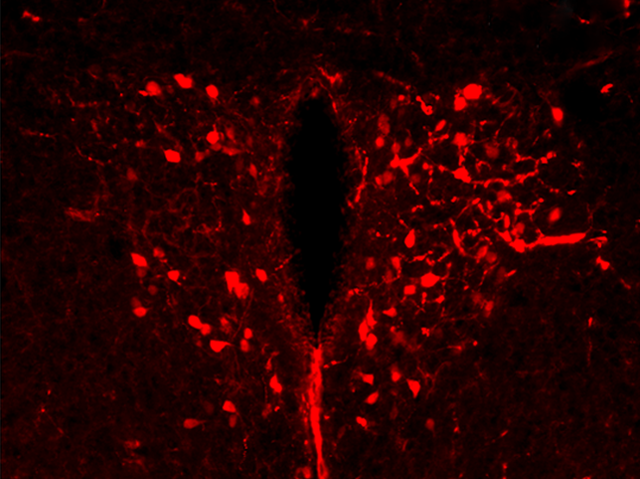

How is body weight regulated? There’s an area of the brain, called the hypothalamus that detects messages from fat cells and responds by sending signals to increase or decrease eating according to the message received. The messages are relayed via brain cells (shown in red) that contain an active gene intriguingly called single-minded 1 (sim1). Mice that lack the sim1 gene are obese because they overeat. But mice that also lack all the cells that would contain active sim1 in the hypothalamus not only overeat – their metabolism, or energy expenditure, is lower too. So energy expenditure is controlled from the same region but not by the sim1 gene. Researchers are increasingly aware of reduced metabolism in weight control but don’t yet fully understand it, although one possibility is that it’s caused by reduced heat production. Understanding this will lead to improved treatments for obesity.